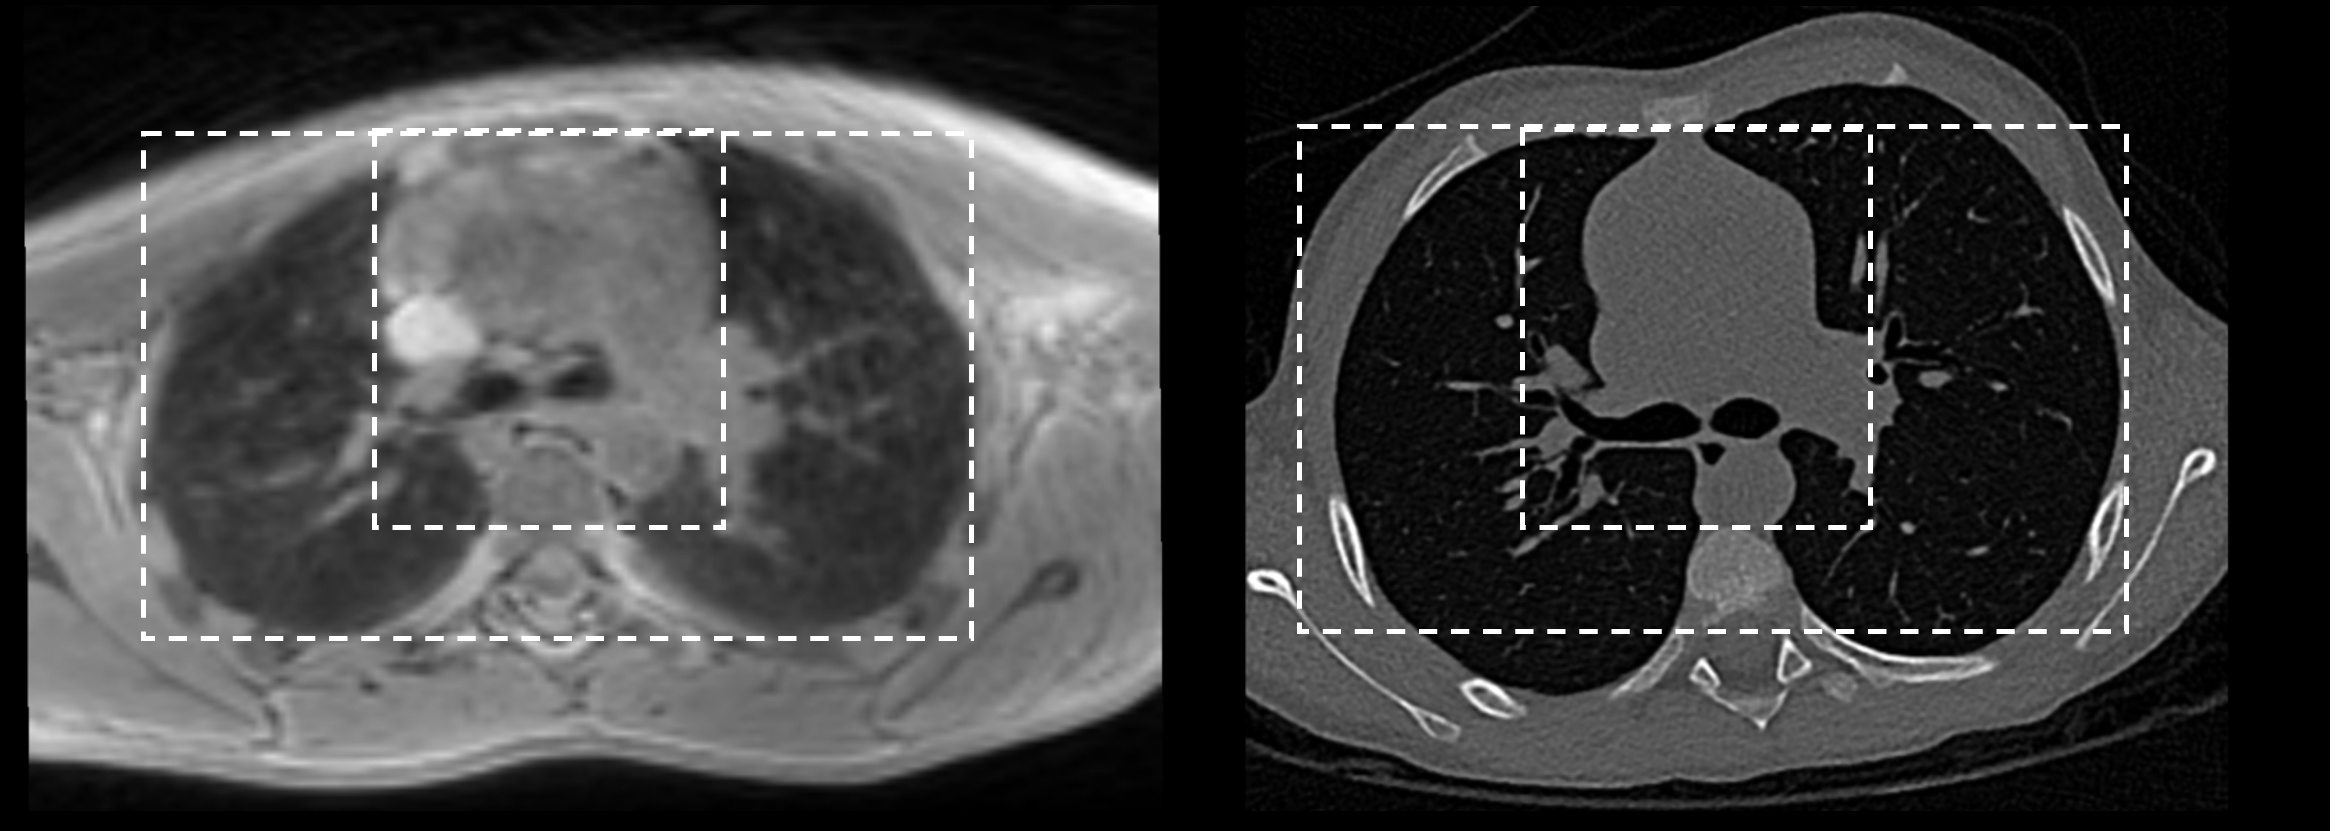

One recent work RegGAN [Kong et al.(2021)Kong, Lian, Huang, Hu, Zhou, et al.] explored directional registration in image synthesis on datasets with simulated misalignment; however, the real-life setting often involves large deformation between pairs (e.g., Figure 1), causing difficulty in learning unique one-to-one mapping due to a large number of local minima [Christensen and Johnson(2001)]. The resulting correspondence ambiguity and asymmetric mapping error would add to pixel-wise error in supervised methods, causing a major challenge in generative modelling. The second challenge is the degraded image fidelity caused by the influence of spatial misalignment during the adversarial process. To further elaborate on the issue, the discriminator in RegGAN may recognise the real/fake images purely based on spatial morphology rather than intensity characteristics, thus leading to suboptimal image fidelity.

Refer to caption

Figure 1: Substantial misalignment in lung MRI-CT pairs due to respiratory motion.

In this paper, we propose a Deformation-aware GAN (DA-GAN) to jointly address the above two synthesis challenges when image pairs are substantially misaligned. Firstly, inspired by the capacity of symmetric registration to jointly estimate invertible bidirectional transformation, we propose a multi-objective inverse consistency to comprehensively investigate how to cohesively incorporate symmetric registration into an image generation network. To further improve degraded image fidelity in an adversarial process, we design a deformation-aware adversarial loss, which leverages the outputs from symmetric registration to guide the discriminator to learn the intensity characteristics (that are disentangled from the mismatched spatial morphology). We comprehensively validated our proposed DA-GAN on two datasets, including a public simulation brain dataset with 6 levels of simulated misalignments, and a real-world lung MRI-CT dataset with challenging respiratory-motion misalignments.